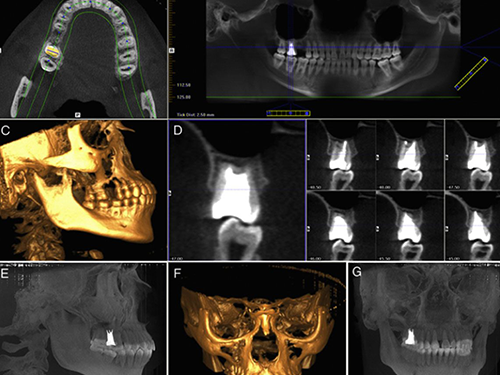

Programas de estudio

Adaptados a los tiempos modernos en los que las plataformas tecnológicas son una herraienta esencial.